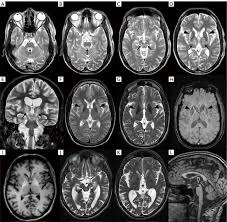

Wilson disease mri brain. MRI studies have identified focal abnormalities in the white matter pons and deep. Positive findings believed secondary to this condition were found in 15 subjects. Wilson disease hepatolenticular degeneration is an autosomal recessive defect in cellular copper transport.

6 8 Neurologic WD is one of the main forms of the disease. In Wilson disease WD T2T2weighted T2w MRI frequently shows hypointensity in the basal ganglia that is suggestive of paramagnetic deposits. It is currently unknown whether this hypointensity is related to copper or iron deposition.

Interval changes on follow-up MR imaging were also closely correlated with clinical findings and. MRI of the brain appears to be more sensitive than CT scanning in detecting early lesions of Wilson disease. The face of the giant panda sign panda sign of the midbrain or double-panda sign is a characteristic pandas face appearance in magnetic resonance imaging MRI images of people with Wilsons disease.

1 In addition a second miniature panda face can be seen in the high signal abnormality in the pons figure C. To describe the spectrum of brain abnormalities in Wilson disease hepatolenticular degeneration as depicted at magnetic resonance MR imaging and computed tomography CT and to relate these findings to neurologic and hepatologic abnormalities.

The National Organizations for Rare Disorders NORD reported that 1 in every 30000 to 40000 people in the world are affected by WD 1. To describe the spectrum of brain abnormalities in Wilson disease hepatolenticular degeneration as depicted at magnetic resonance MR imaging and computed tomography CT and to relate these findings to neurologic and hepatologic abnormalities. 3 5 WD leads to intracellular copper accumulation causing damage to many organs especially the brain. Dysarthria tremor ataxia rigiditybradykinesia and choreadystonia. In Wilson disease WD T2T2weighted T2w MRI frequently shows hypointensity in the basal ganglia that is suggestive of paramagnetic deposits. Wilson disease also known as hepatolenticular degeneration is a multisystem disease due to abnormal accumulation of copper. It is found worldwide with a prevalence of approximately 1 case in 30000 live births in most populations. Patients neurological symptoms brain MRI features and laboratory findings were noted. The patients were scanned using spin-echo SE sequences.

To describe the spectrum of brain abnormalities in Wilson disease hepatolenticular degeneration as depicted at magnetic resonance MR imaging and computed tomography CT and to relate these findings to neurologic and hepatologic abnormalities. Positive findings believed secondary to this condition were found in 15 subjects. It is found worldwide with a prevalence of approximately 1 case in 30000 live births in most populations. Thirty-eight patients with biochemically proven Wilsons disease underwent magnetic resonanceimaging MRI of the brain as well as neurological examinations. Fifty patients with Wilson disease participated in the cross-sectional. The face of the giant panda sign panda sign of the midbrain or double-panda sign is a characteristic pandas face appearance in magnetic resonance imaging MRI images of people with Wilsons disease. 1 In addition a second miniature panda face can be seen in the high signal abnormality in the pons figure C.